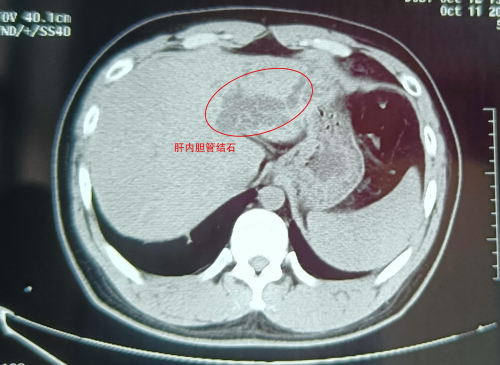

武汉的刘先生怎么也没想到,看似普通的腹痛,竟险些让自己丢了肝!近日,这位肝胆系统布满结石的“小黄人”,紧急求助于武汉京都结石医院。幸运的是,因为手术处理得当,刘···